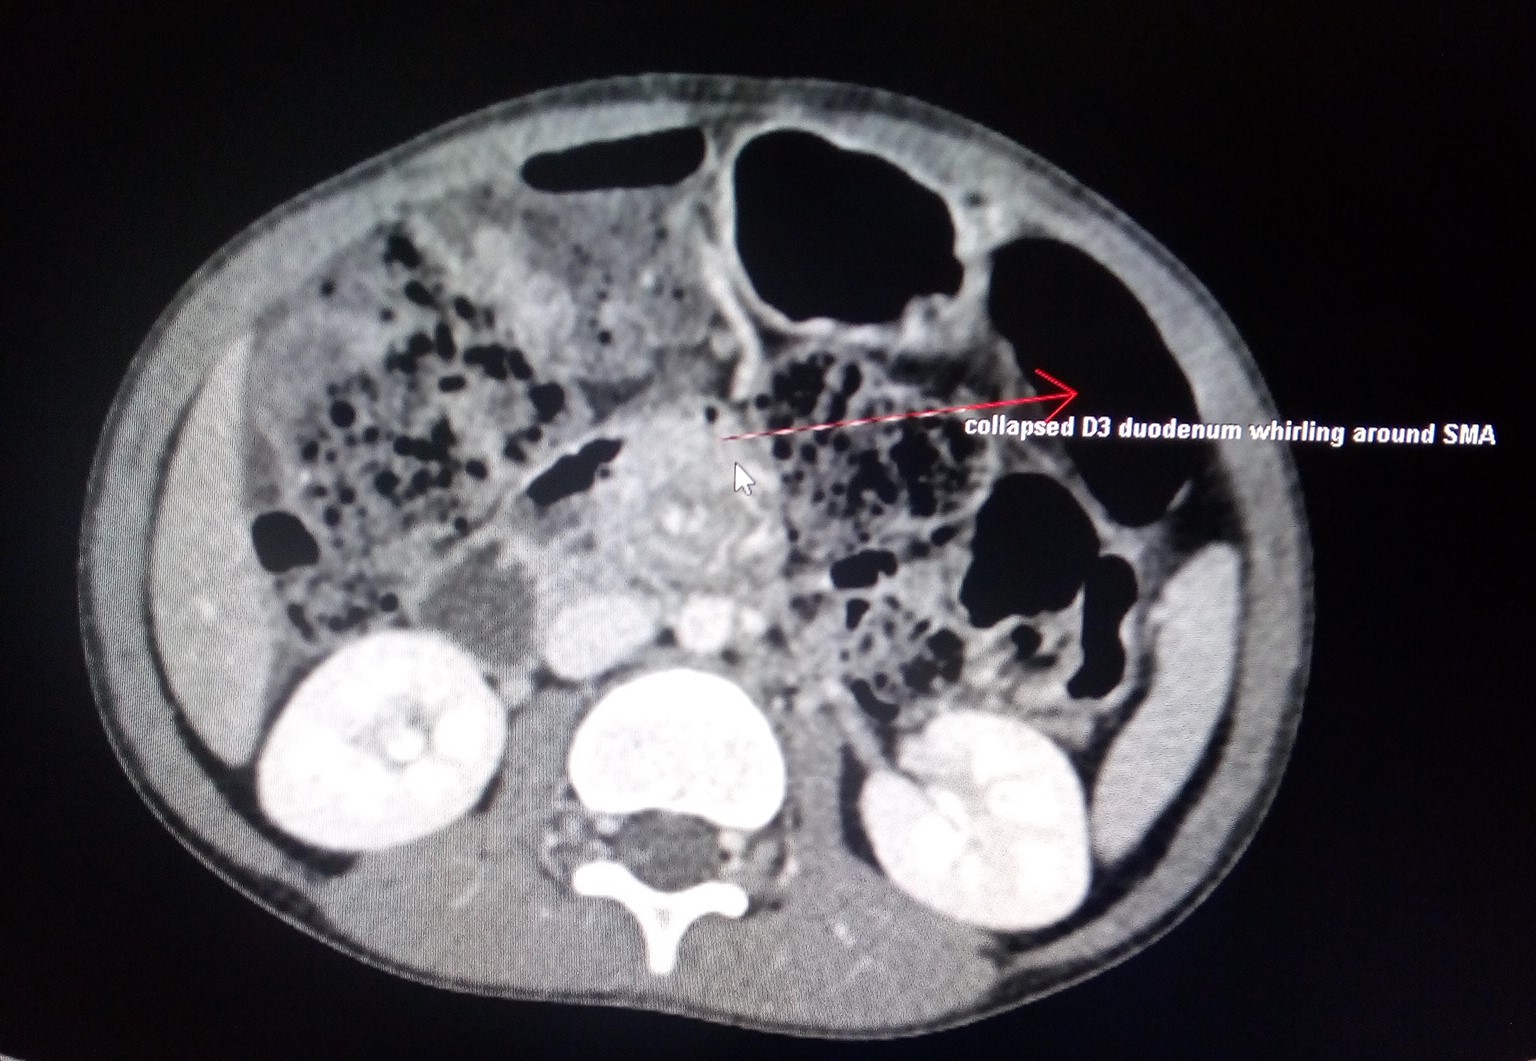

Midgut Volvulus CT Sumer's Radiology Blog Corkscrew Duodenum The corkscrew sign (figure 1b) refers to the twisted configuration of the proximal small bowel loops seen on upper gastrointestinal (ugi) in. In patients with malrotation and volvulus, the. The child may also show a corkscrew effect diagnosing volvulus or complete duodenal obstruction, with the small bowel looping entirely on the right side of the abdomen. Midgut volvulus is a. Corkscrew Duodenum.

Midgut Volvulus CT Sumer's Radiology Blog Corkscrew Duodenum Corkscrew duodenum in malrotation with a midgut volvulus. The helix type appearance of the midgut seen in malrotation with midgut volvulus has been likened to the metallic helix of a. Imaging spectrum of the duodenum on fluoroscopy A corkscrew appearance of the duodenum and proximal jejunum (figure 1) was pathognomonic for midgut volvulus. The corkscrew sign (figure 1b) refers to. Corkscrew Duodenum.